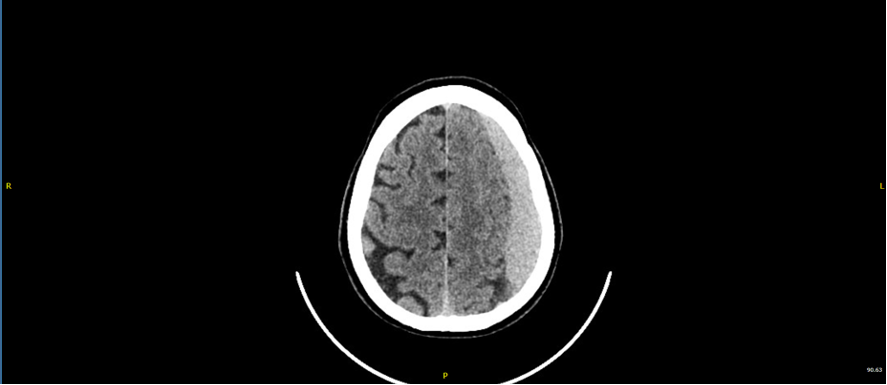

• TAC de cráneo: Hematoma subdural frontoparietal izdo, de probable evolución subaguda. Efecto de masa sobre parénquima cerebral, con obliteración de surcos de la convexidad izda, con mínimo desplazamiento de línea media (3 mm).

• Hematoma subdural frontoparietal izquierdo subagudo postraumático

Se comenta con el servicio de Neurocirugía consideran no patología quirúrgica urgente, indican ingreso vigilancia neurológica, profilaxis anticomicial y TAC de cráneo control en 72 horas.

Persiste colección hemática con puntos de resangrado. El paciente persiste pauci/asintomatico se plantea puede beneficiarse de embolización de meningea media.